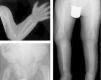

La serie ósea radiológica mostró malformaciones metafisarias de huesos largos (fig. 1) y ensanchamiento de costillas. El estudio bioquímico confirmó la existencia de niveles disminuidos de fosfatasa alcalina sérica, junto con un notable incremento de los niveles sus sustratos: piridoxina y fosfoetanolamina (formas inorgánicas de fósforo), con niveles normales de 25-OH-vitamina D y del resto de parámetros del metabolismo fosfocálcico estudiados (tabla 1). La secuenciación del gen codificante de la fosfatasa alcalina (ALPL), detectó la presencia en heterocigosis compuesta de las mutaciones conocidas c.542C>T (p.S181L) y c.644T>C (p.I215T), confirmándose el diagnóstico de hipofosfatasia.

Marcada alteración en metáfisis de huesos largos (proximales de ambos húmeros, distales de ambos radios y cúbitos y proximales de ambos fémures, tibias y peronés), que se encuentran ensanchadas, con pérdida de densidad ósea, trabéculas groseras y proyecciones radiolucentes que se extienden desde la fisis hacia la metáfisis. Reacción perióstica lineal en el radio izquierdo.